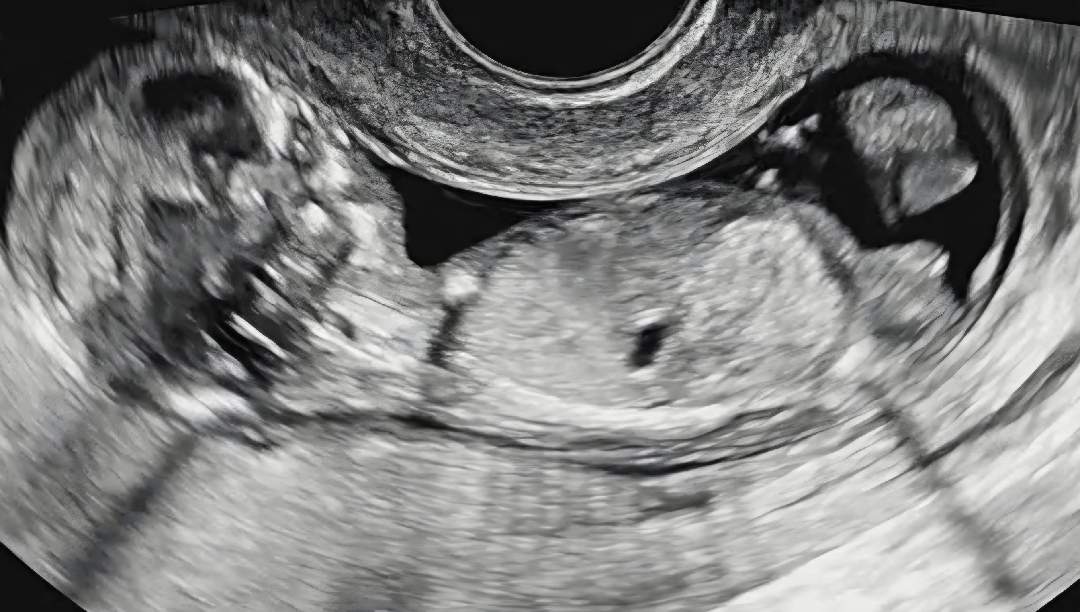

각도법 봐주세용

딸일까요 아들일까요~?

아들 같아용

아들에 한표요

아들 같아요